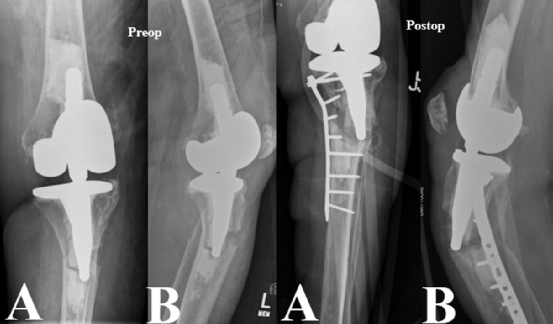

图3. Felix II型骨折术前、术后的正侧位X光片